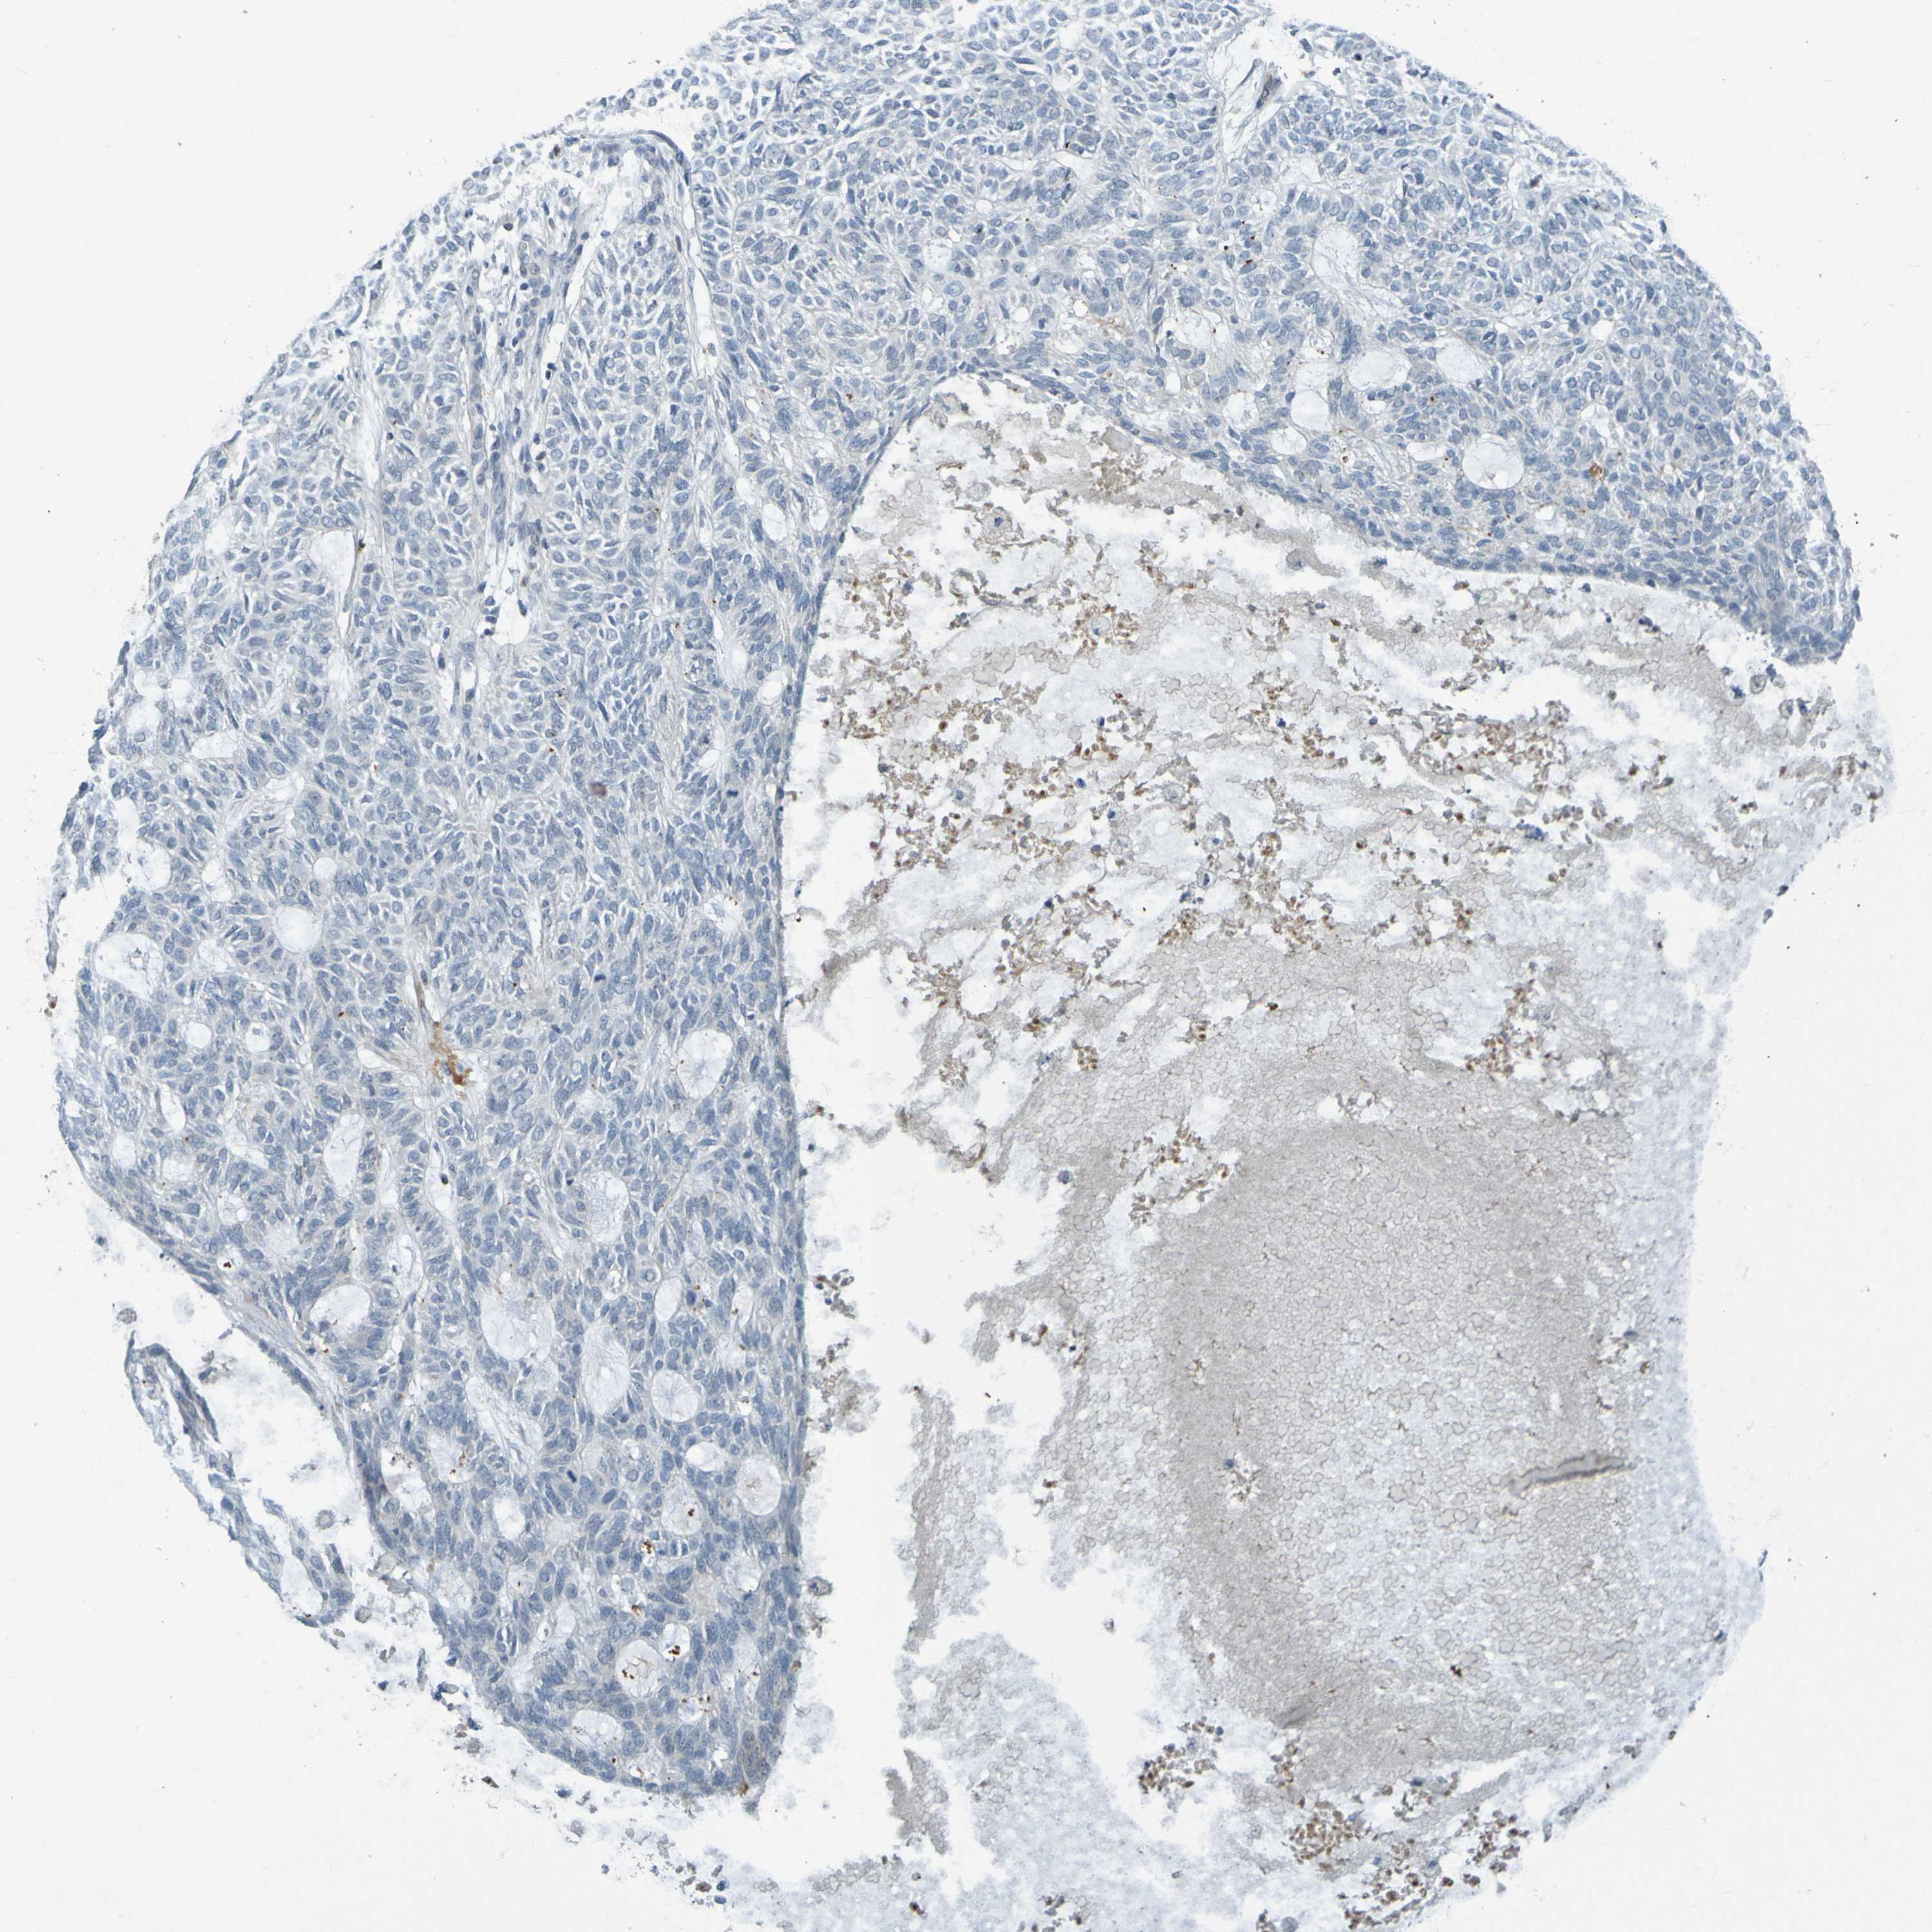

CANCER SKIN CANCER Show tissue menu

Basal cell and squamous cell cancer

SKIN CANCER - Protein expressioni

A mouse-over function shows sample information and annotation data. Click on an image to view it in a full screen mode. Samples can be filtered based on level of antibody staining by selecting one or several of the following categories: high, medium, low and not detected. The assay and annotation is described here.

Each image is clickable and will lead to virtual microscopy that enables deeper exploration of all samples and also displays staining intensity scores, fraction scores and subcellular localization as well as patient and tissue information for each sample.

Antibody HPA071391

Antibody CAB013120

Basal cell carcinoma

Squamous cell carcinoma, NOS